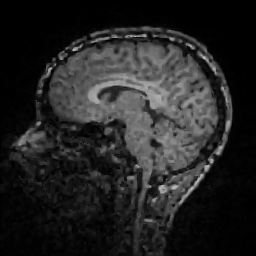

Improving image reconstruction from a sparse set of known pixels was the main motivation behind our work. Therefore, we applied it to two well-known natural images, lena and peppers, as well as to a medical image, a slice of a weighted brain MR scan (t1slice). For lena, we kept a random subset of only of the pixels. Due to the lower resolution of the peppers and t1slice images, we kept and , respectively.

Results for lena are shown in Figure 2, for peppers in Figure 3, and for t1slice in Figure 4. A quantitative evaluation in terms of MSE and AAE is presented in Table 4.1. In terms of the numerical results, our proposed method produced a more accurate reconstruction than any of the competing approaches. Visually, there is a clear difference between second-order (EED) and fourth-order approaches (Li1, Li2, FOEED). Especially, we found that the shapes of edges were reconstructed more accurately. For example, we noticed this around the shoulder and hat in the lena image (Figure 2). Similarly, the white and grey matter boundaries were better separated in the t1slice (Figure 4).